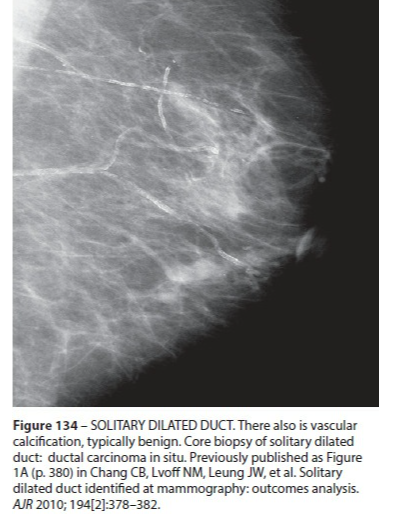

Ectasie Canlaire Solitaire

- Rare